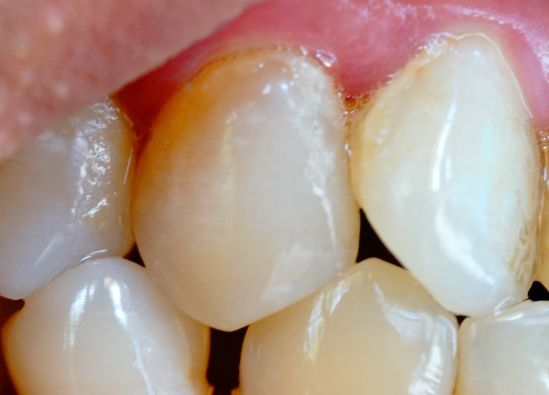

牙齒表面的牙釉質(zhì)掉了還可以修復(fù)嗎?

牙釉質(zhì)一旦掉了(即發(fā)生實(shí)質(zhì)性缺損)是無(wú)法再生的,因?yàn)檠烙再|(zhì)是人體中唯一沒(méi)有細(xì)胞、沒(méi)有血管、不能自我修復(fù)的硬組織。但“不能再生”不等于“不能修復(fù)”——現(xiàn)代牙科有多種有效方法可以功能性或美觀性地修復(fù)牙釉質(zhì)…